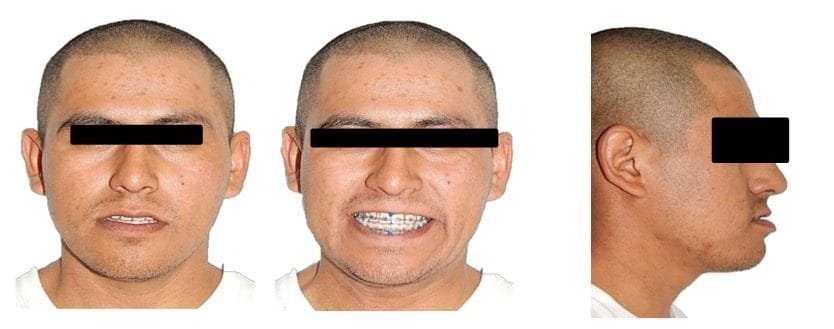

Análisis extraoral

Se observa en las fotografías de frente, cara larga con un mentón desviado hacia la derecha. Tanto en reposo como en sonrisa, en la de perfil una notable proyección del mentón respecto al maxilar y en la frontal se evidencia la poca proyección de la zona malar y tercio medio de la cara. (Figs. 1, A-C)

Fig.1 Fotografías extraorales de Inicio. A) Frente. B) Sonrisa. C) Perfil.